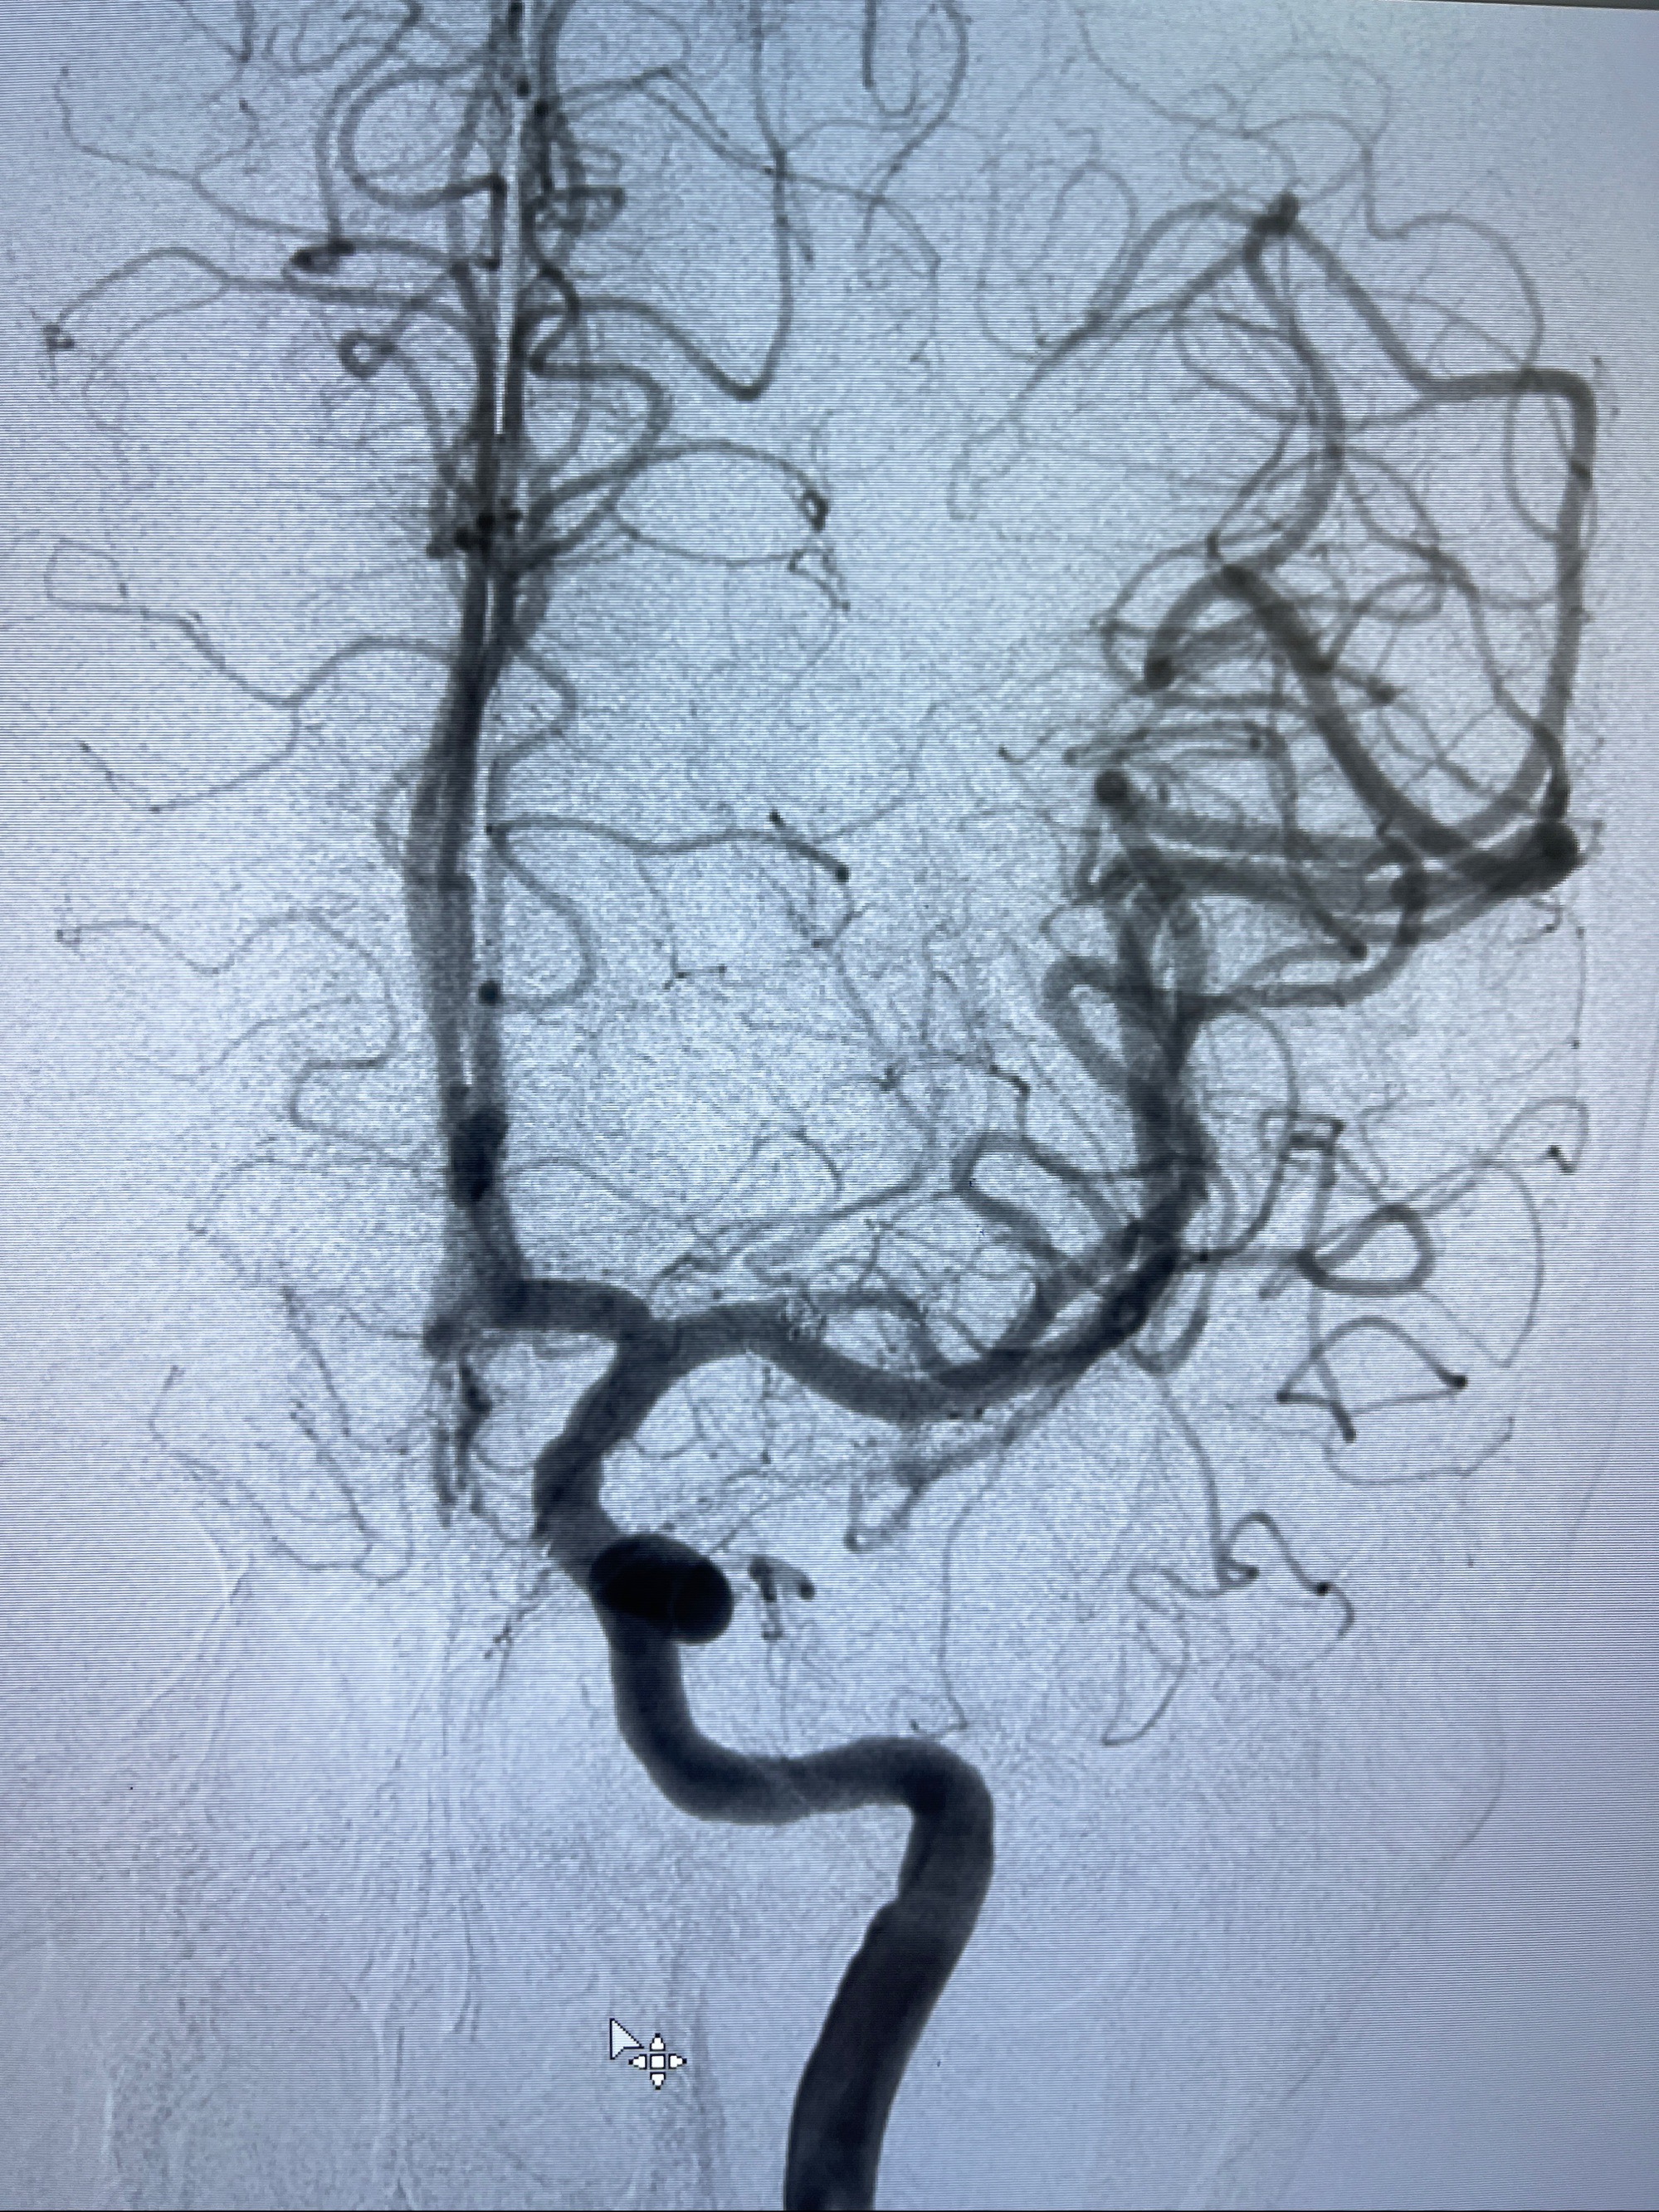

2023-08-14DSA:

左侧大脑中动脉动脉瘤,约2.6-2.8-3.4-2mm大小(瘤颈部、瘤体部、瘤高)

1.左侧大脑中动脉动脉瘤,约2.6-2.8-3.4-2mm大小(瘤颈部、瘤体部、瘤高)

2.外科手术夹闭or介入支架辅助栓塞

麻醉苏醒佳,遵嘱动作